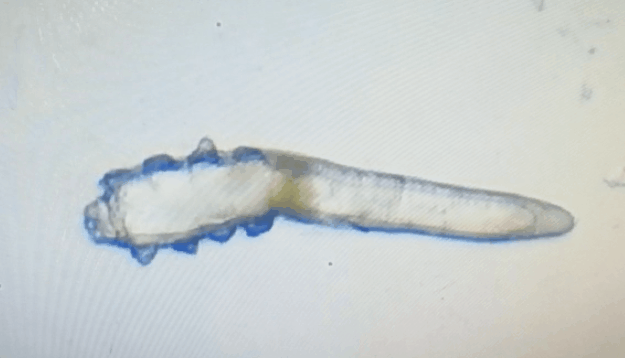

這就不得不提到眼科醫(yī)生經(jīng)常使用的螨蟲檢測工具——螨蟲鏡檢。它通過顯微利器,無死角全方位掃描你的睫毛,讓螨蟲無處遁形。

林女士是一家公司的白領(lǐng),常常需要濃妝出席各種會議,然而光鮮亮麗的背后,林女士的眼睛正遭受著和陳先生同樣的癥狀。在螨蟲鏡檢中,當(dāng)看到自己的睫毛上爬滿了十幾只透明的生物-螨蟲,林女士嚇了一跳。幸而,經(jīng)過廈門眼科中心干眼中心的治療,林女士解決了多年的眼睛干癢問題。